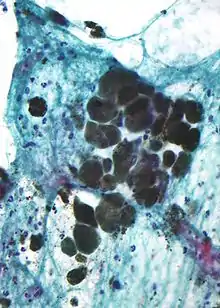

Microscopic appearance

Melanin is brown, non-refractile, and finely granular with individual granules having a diameter of less than 800 nanometers. This differentiates melanin from common blood breakdown pigments, which are larger, chunky, and refractile, and range in color from green to yellow or red-brown. In heavily pigmented lesions, dense aggregates of melanin can obscure histologic detail. A dilute solution of potassium permanganate is an effective melanin bleach.[50]